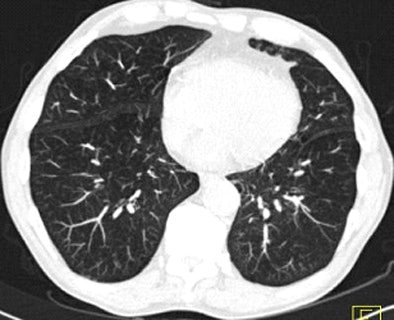

![]() |

| Images above and below show a spiculated nodule measuring 169 mm3 at baseline low-dose CT screening. Bottom image, acquired four years after the baseline scan, shows that the nodule has resolved. All images courtesy of Dr. Rosemarijn Vliegenthart. |